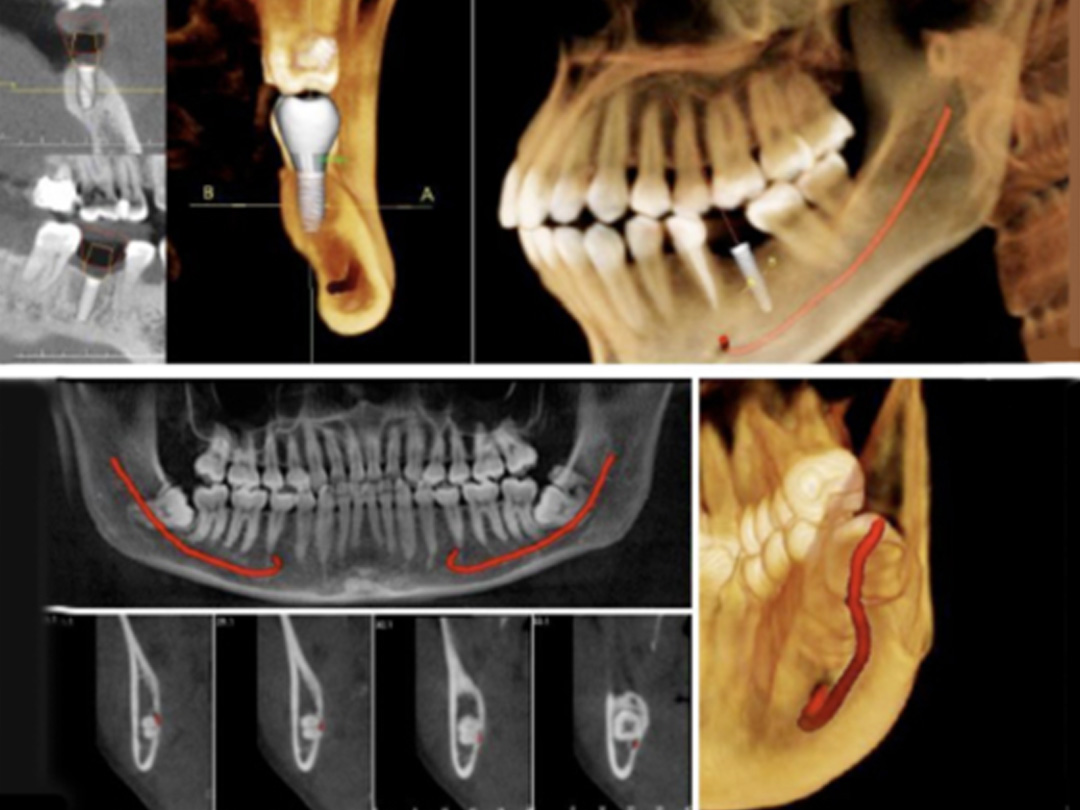

- 高解析AI斷層掃瞄儀:完整顯示骨質狀況及重要神經血管,使植牙都在最安全、最穩固的位置。

ALL ON全口重建是由4-6 顆植體(依條件而定)成,專為多顆缺牙或全口無牙患者設計的創新全口重建技術,僅需4-6 支植體即可支撐一整排固定式假牙,大幅減少手術次數與成本,並縮短療程時間。

免補骨/少補骨即可植牙,降低手術複雜度